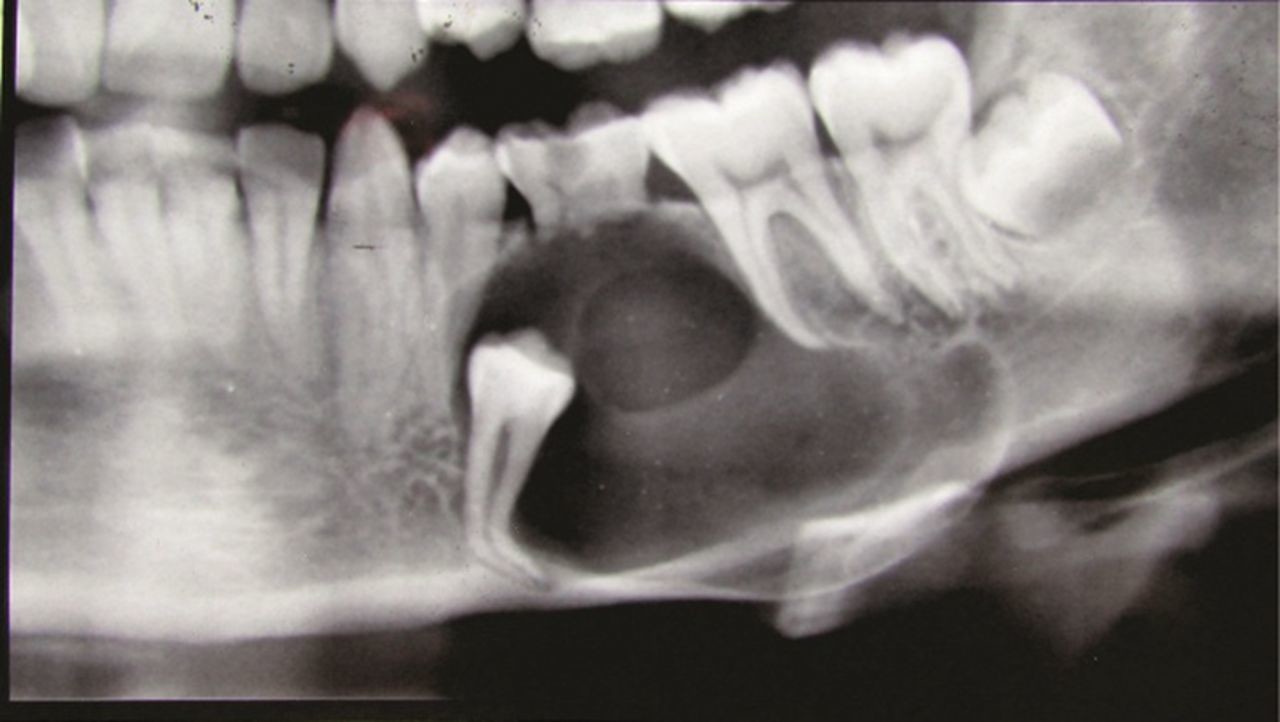

How is it diagnosed?

Small dentigerous cysts often go unnoticed until you have a dental X-ray. If your dentist notices an unusual spot on your dental X-ray, they may use a CT scan or MRI scan to make sure it’s not another type of cyst, such as a periapical cyst or an aneurysmal bone cyst.

In some cases, including when the cyst is larger, your dentist may be able to diagnose a dentigerous cyst just by looking at it.